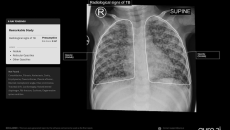

Its chest X-ray analysis AI tool is the first to receive Europe's clearance for use in children aged 0-3.